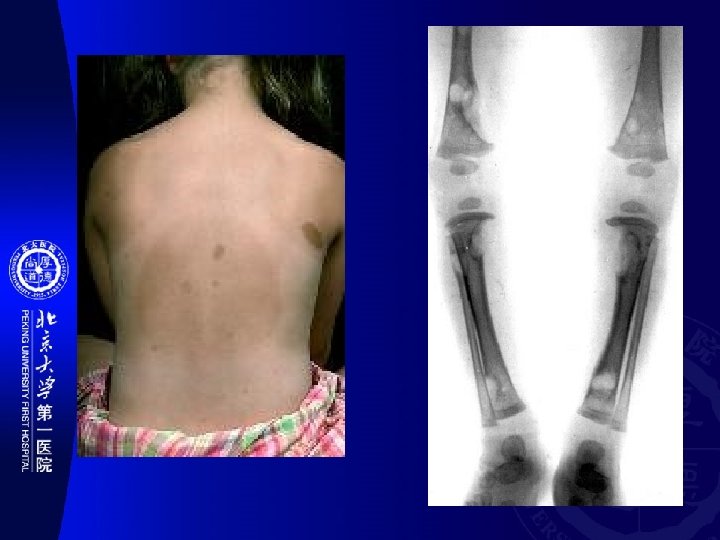

Jaffe-Campanacci Syndrome • Jaffe–Campanacci syndrome is one of the disorders associated with café au

Jaffe-Campanacci Syndrome • Jaffe–Campanacci syndrome is one of the disorders associated with café au lait macules (CALMs). 表现为精神迟缓、全身长骨多发非 骨化性纤维瘤、性腺功能减退及隐睾、或下颌 骨巨细胞肉芽肿。 • 近年来研究认为与神经纤维瘤病相关。